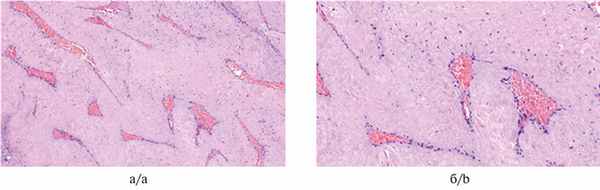

По результатам гистологического и иммуногистохимического исследований (от 21.05.18) подтвержден диагноз типичной юношеской ангиофибромы основания черепа (рис. 3). Рис. 3. Юношеская ангиофиброма. Окраска гематоксилином и эозином. Типичная гистологическая картина опухоли — среди малоклеточной фиброзной ткани располагаются тонкостенные дилатированные сосуды с явлениями микроваскулярной пролиферации, просвет сосудов заполнен эритроцитами. а — ув. 100; б — ув. 200.